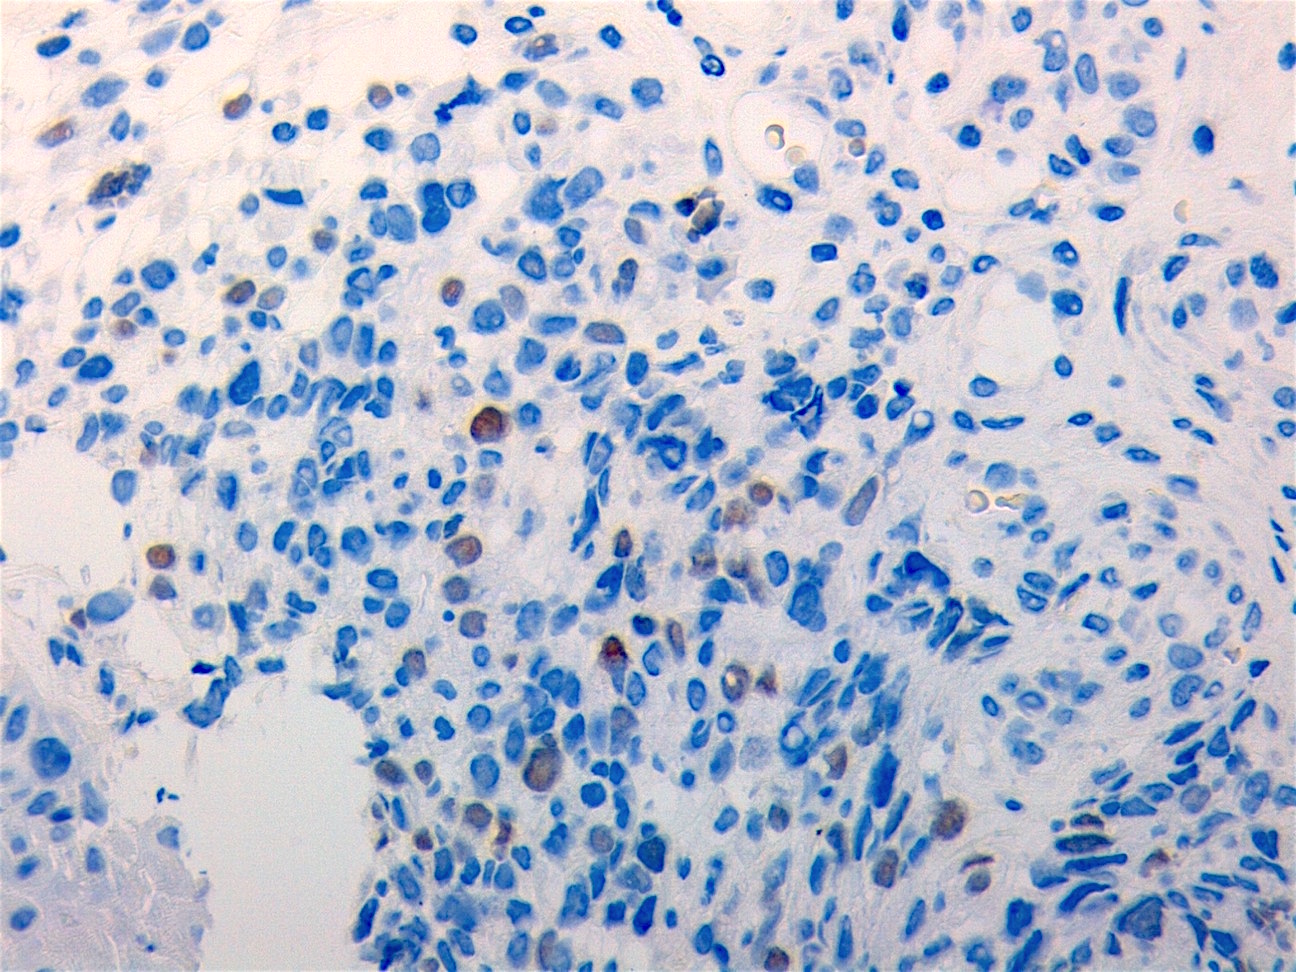

Microscopic (histologic) images

Contributed by Erdener Özer, M.D., Ph.D. and Mark R. Wick, M.D.

Contributed by Carolina Martinez Ciarpaglini, M.D., Ph.D. (Case #276) - tonsillar mass

AFIP images - anaplastic rhabdomyosarcoma

AFIP images - botryoid variant

Positive stains

- Desmin, MyoD1 or myogenin are critical to document (Pathol Oncol Res 2008;14:233)

- Without myogenic differentiation (MyoD1 or myogenin), it is very difficult to diagnose embryonal rhabdomyosarcoma

- These stains will be less diffuse than in alveolar rhabdomyosarcoma and can be extremely focal